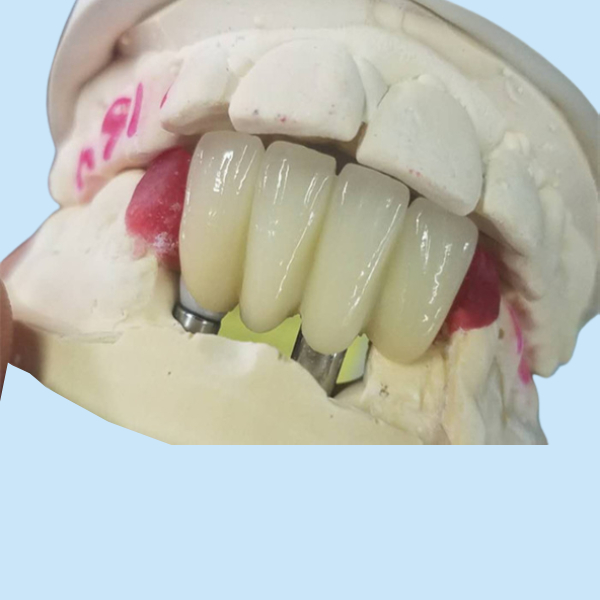

Strong Ti Base Milling Dental Implant Crowns Tooth Supported Bridge

Implant Abutment Meaning:

The abutment of an implant is literally the part where the base of the implant connects. Strictly speaking, the name should refer to the abutment of the implant. So what is an implant abutment? We know that an implant consists of many parts, including implants, abutments, and dentures. In fact, an implant abutment is simply an abutment, which is mounted on an implant platform anchored in the bone and extends into the oral cavity to connect, support and fix the prosthesis or implant superstructure. This is why it is also called a transmucosal abutment.

Titanium Abutment Features:

1. The material of titanium abutment is harder than spring titanium abutment and all-ceramic abutment, and it is very durable.

2. Wear-resistant and corrosion-resistant.

3. Cost-effective

4. It can withstand force in combination with human bones, and is a metal material with relatively good biological properties.

Dental Implant Crown Parameters: